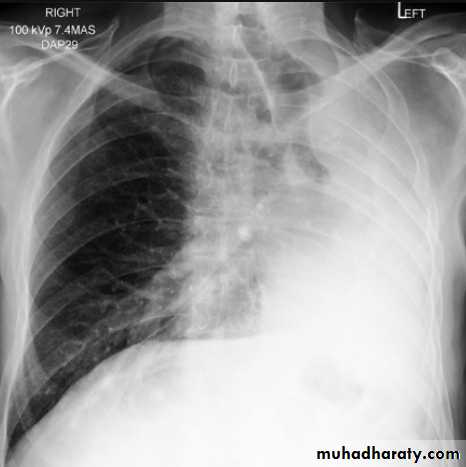

Left lower lobe collapse has distinctive features, and can be readily identified on frontal chest radiographs, provided attention is paid to the normal cardiomediastinal contours. The shadow cast by the heart does however make it harder to see than the right lower lobe collapse

Radiographic features

Left lower lobe collapse

is readily identified in a well penetrated film of a patient with normal sized heart, but can be challenging in the typical patient with collapse, namely unwell patients, with portable (AP) often under-penetrated films, often with concomitant cardiomegaly. Features to be observed include :

triangular opacity in the posteromedial aspect of the left lung

edge of collapsed lung may create a 'double cardiac contour'

left hilum will be depressed

loss of the normal left hemidaphgragmatic outline

loss of the outline of the descending aorta

Non-specific signs indicating left sided atelectasis are usually also be present including:

elevation of the hemidiaphragm

crowding of the left sided ribs

shift of the mediastinum to the left

On lateral projection the left hemidiaphragmatic outline is lost posteriorly and the lower thoracic vertebrae appear denser than normal (they are usually more radiolucent than the upper vertebrae) .